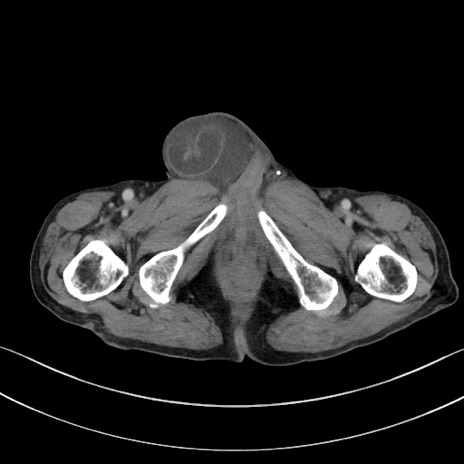

症例3(横断像)

【症例】 70歳代男性

【主訴】右鼠径部腫瘤、疼痛

【現病歴】本日朝より上記主訴あり、受診。

【既往歴】膀胱癌にて膀胱全摘、両側尿管皮膚瘻

【データ】WBC 5600、CRP 0.56